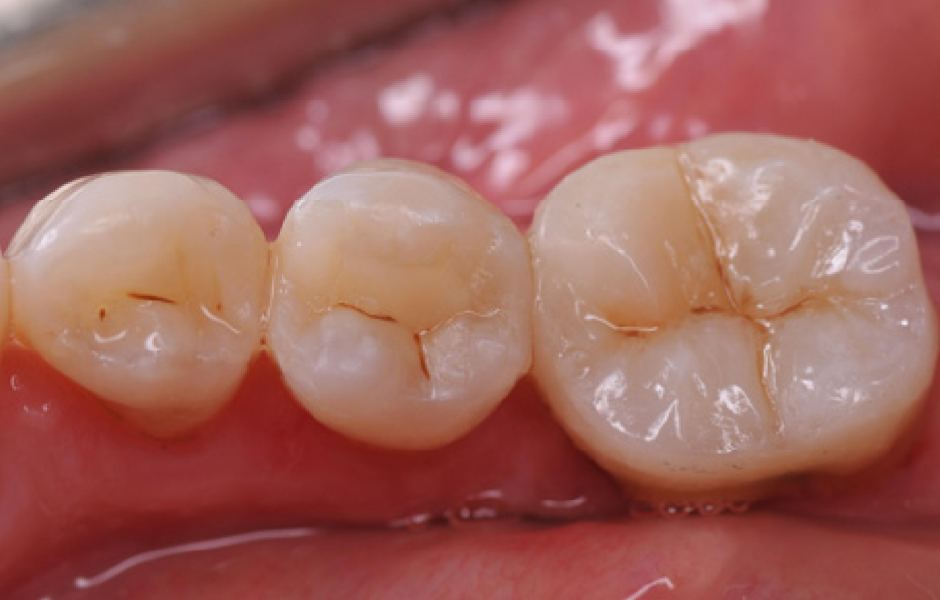

Obr. 13: Kontrola po 1 týdnu. Finální vzhled po týdenní kontrole.